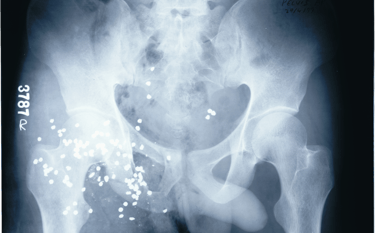

Lead pallets are seen in the pelvic region